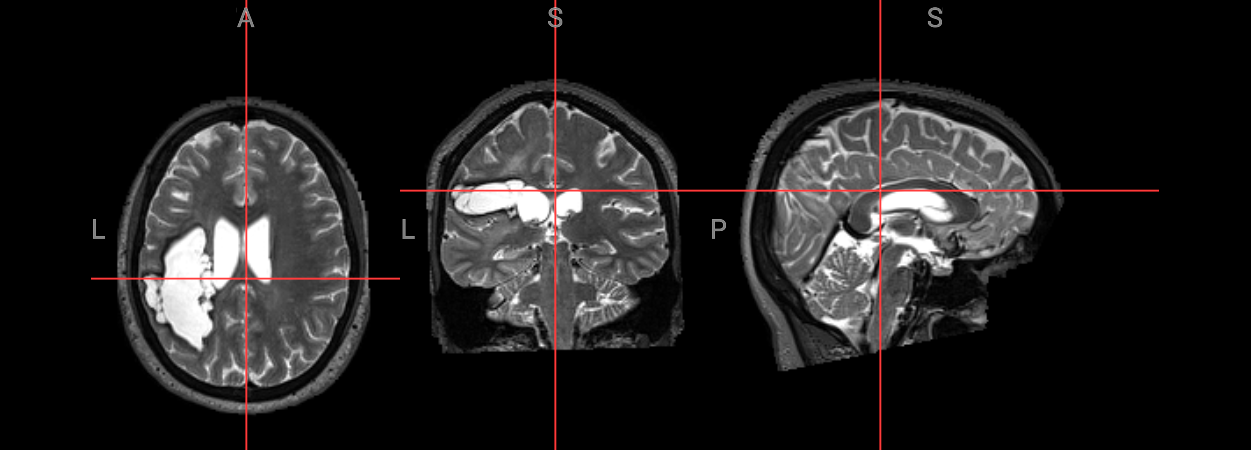

nv_mni_space = NiiVue()

nv_mni_space.load_volumes([{"url": "https://huggingface.co/datasets/neurodeskorg/neurodeskedu/resolve/main/data/examples/structural_imaging/SYNcro/wsub-M2304_ses-262_acq-spc3p2_run-5_T2w_be6e40f42d9c.nii.gz"}])

nv_mni_space

Image(filename='../../static/examples/structural_imaging/SYNcro/mni_wsub-M2304.png')

../../_images/c17486d08a4726cc5516efa5d3605d2f67264333c244e205053878377b42230a.png